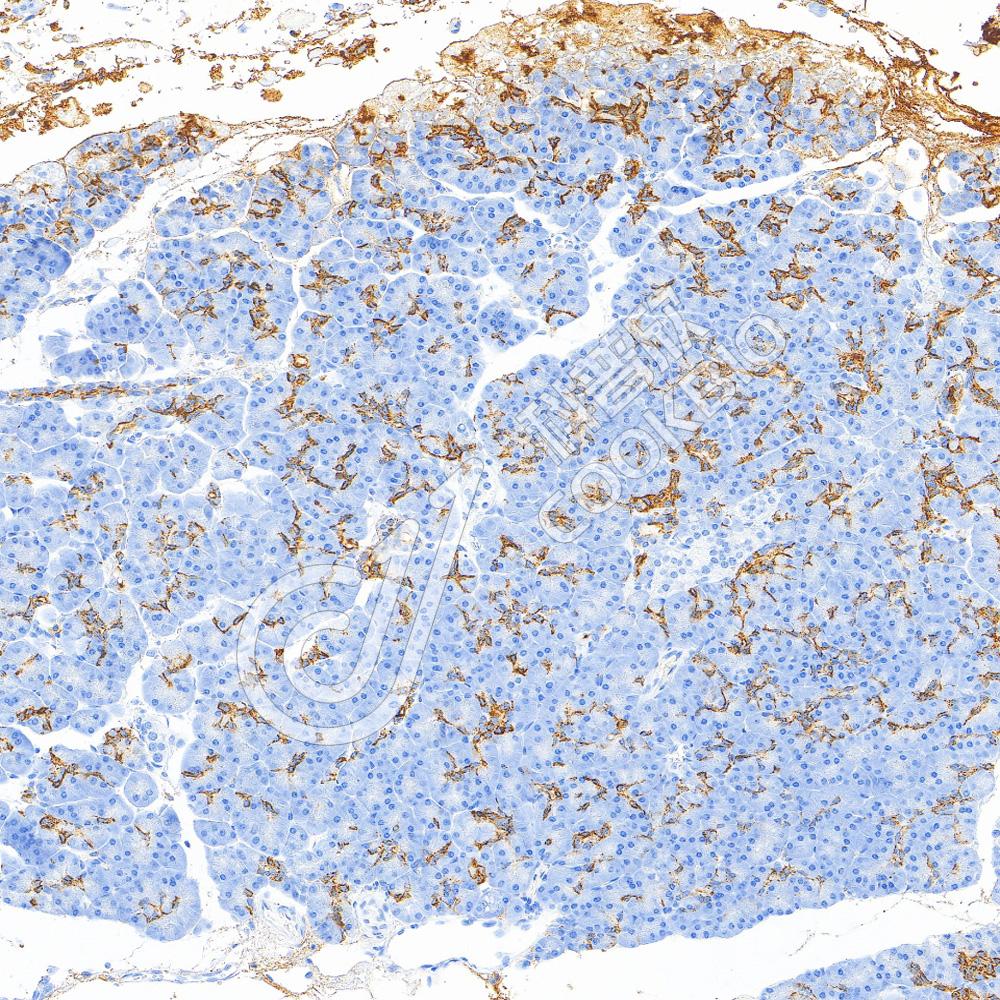

IHC检测CA19-9蛋白(货号 K5450375).

样品: 人胰腺, 4%多聚甲醛 (货号KSG1101) 固定12-24小时.

抗原修复: Tris-EDTA抗原修复液(pH 9.0) (KSG1203), 100℃, 25分钟.

—抗: 1: 500稀释, 4℃ 孵育过夜.

二抗: S-vision免疫组化多聚二抗(山羊抗小鼠), 即用型(货号KB3903), 室温孵育20分钟.